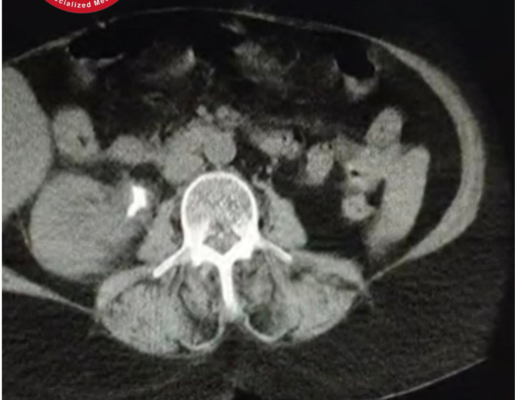

ورم مثانة سطحي تم كشفه مبكرًا بالتنظير البولي

أعراض بولية متكررة ووجود دم خفيف مع البول قادت لاكتشاف ورم مثانة سطحي وعلاجه بالتنظير ضمن عيادة الجراحة البولية في مركز كريم الطبي التخصصي.